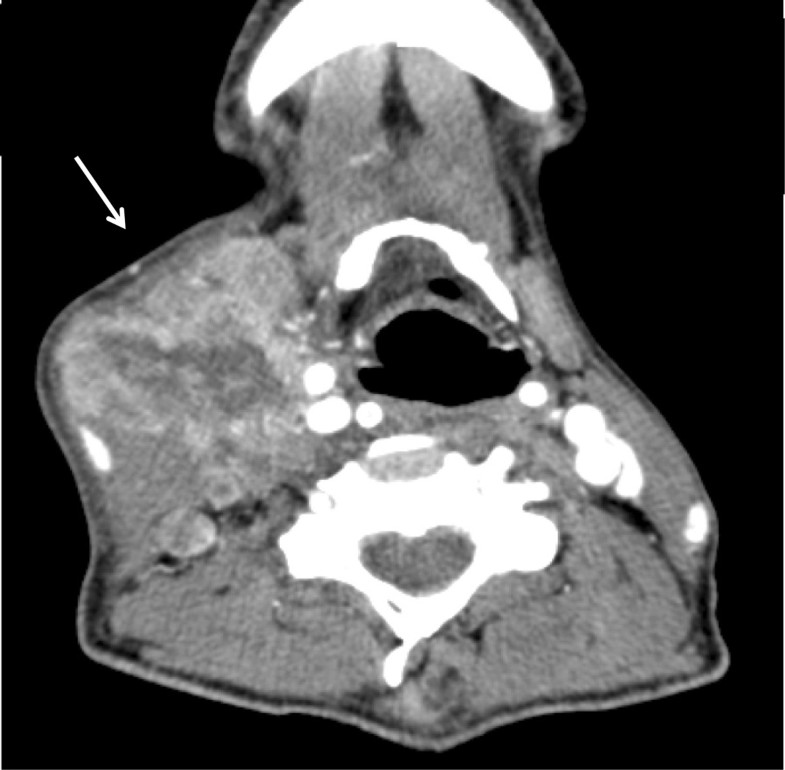

From radiologykey.com

Neuroendocrine Tumors Radiology Key Neuroendocrine Cancer Neck They secrete peptide hormones and present with a. 10 things to know about neuroendocrine tumors. neuroendocrine neoplasms (nens) are rare abnormal growths that originate from widely distributed cells within the neuroendocrine system. Neuroendocrine head and neck tumor survival statistically significantly varied by site and metastatic status, with tumors in the oropharynx and hypopharynx having poorer prognosis. care at. Neuroendocrine Cancer Neck.

Mucosal Cancers Neck Primaries and the Lymph Nodes Radiology Key Neuroendocrine Cancer Neck The tests and procedures you might undergo to diagnose a neuroendocrine tumor will depend on where your tumor is located in your body. neuroendocrine carcinoma (nec) of the head and neck is a rare type of malignancy, accounting for only 0.3% of all head and neck cancers, and its clinicopathological and genomic features. They secrete peptide hormones and present. Neuroendocrine Cancer Neck.

Mucosal Cancers Neck Primaries and the Lymph Nodes Radiology Key Neuroendocrine Cancer Neck 10 things to know about neuroendocrine tumors. neuroendocrine carcinoma (nec) of the head and neck is a rare type of malignancy, accounting for only 0.3% of all head and neck cancers, and its clinicopathological and genomic features. Neuroendocrine head and neck tumor survival statistically significantly varied by site and metastatic status, with tumors in the oropharynx and hypopharynx having. Neuroendocrine Cancer Neck.